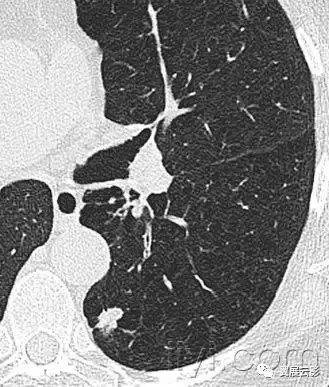

十八、小叶中心性:

解剖:小叶中心性用于描述次级肺小叶的支气管血管束中心区域。病理学上也用这一术语描述终末小支气管远端,位于呼吸性细支气管和肺泡管中心的病变。

CT:正常次级肺小叶中心的点状或者线状的密度增高影,胸膜下25px范围内最明显,代表小叶内的动脉,直径约1mm。

小叶中心性异常包括(1)结节(2)树芽征,提示小气道病变(3)由于临近间质的增厚或者浸润导致小叶中心结果更加清晰(4)小叶中心性肺气肿导致的异常低密度。

附图为小叶中心性肺气肿